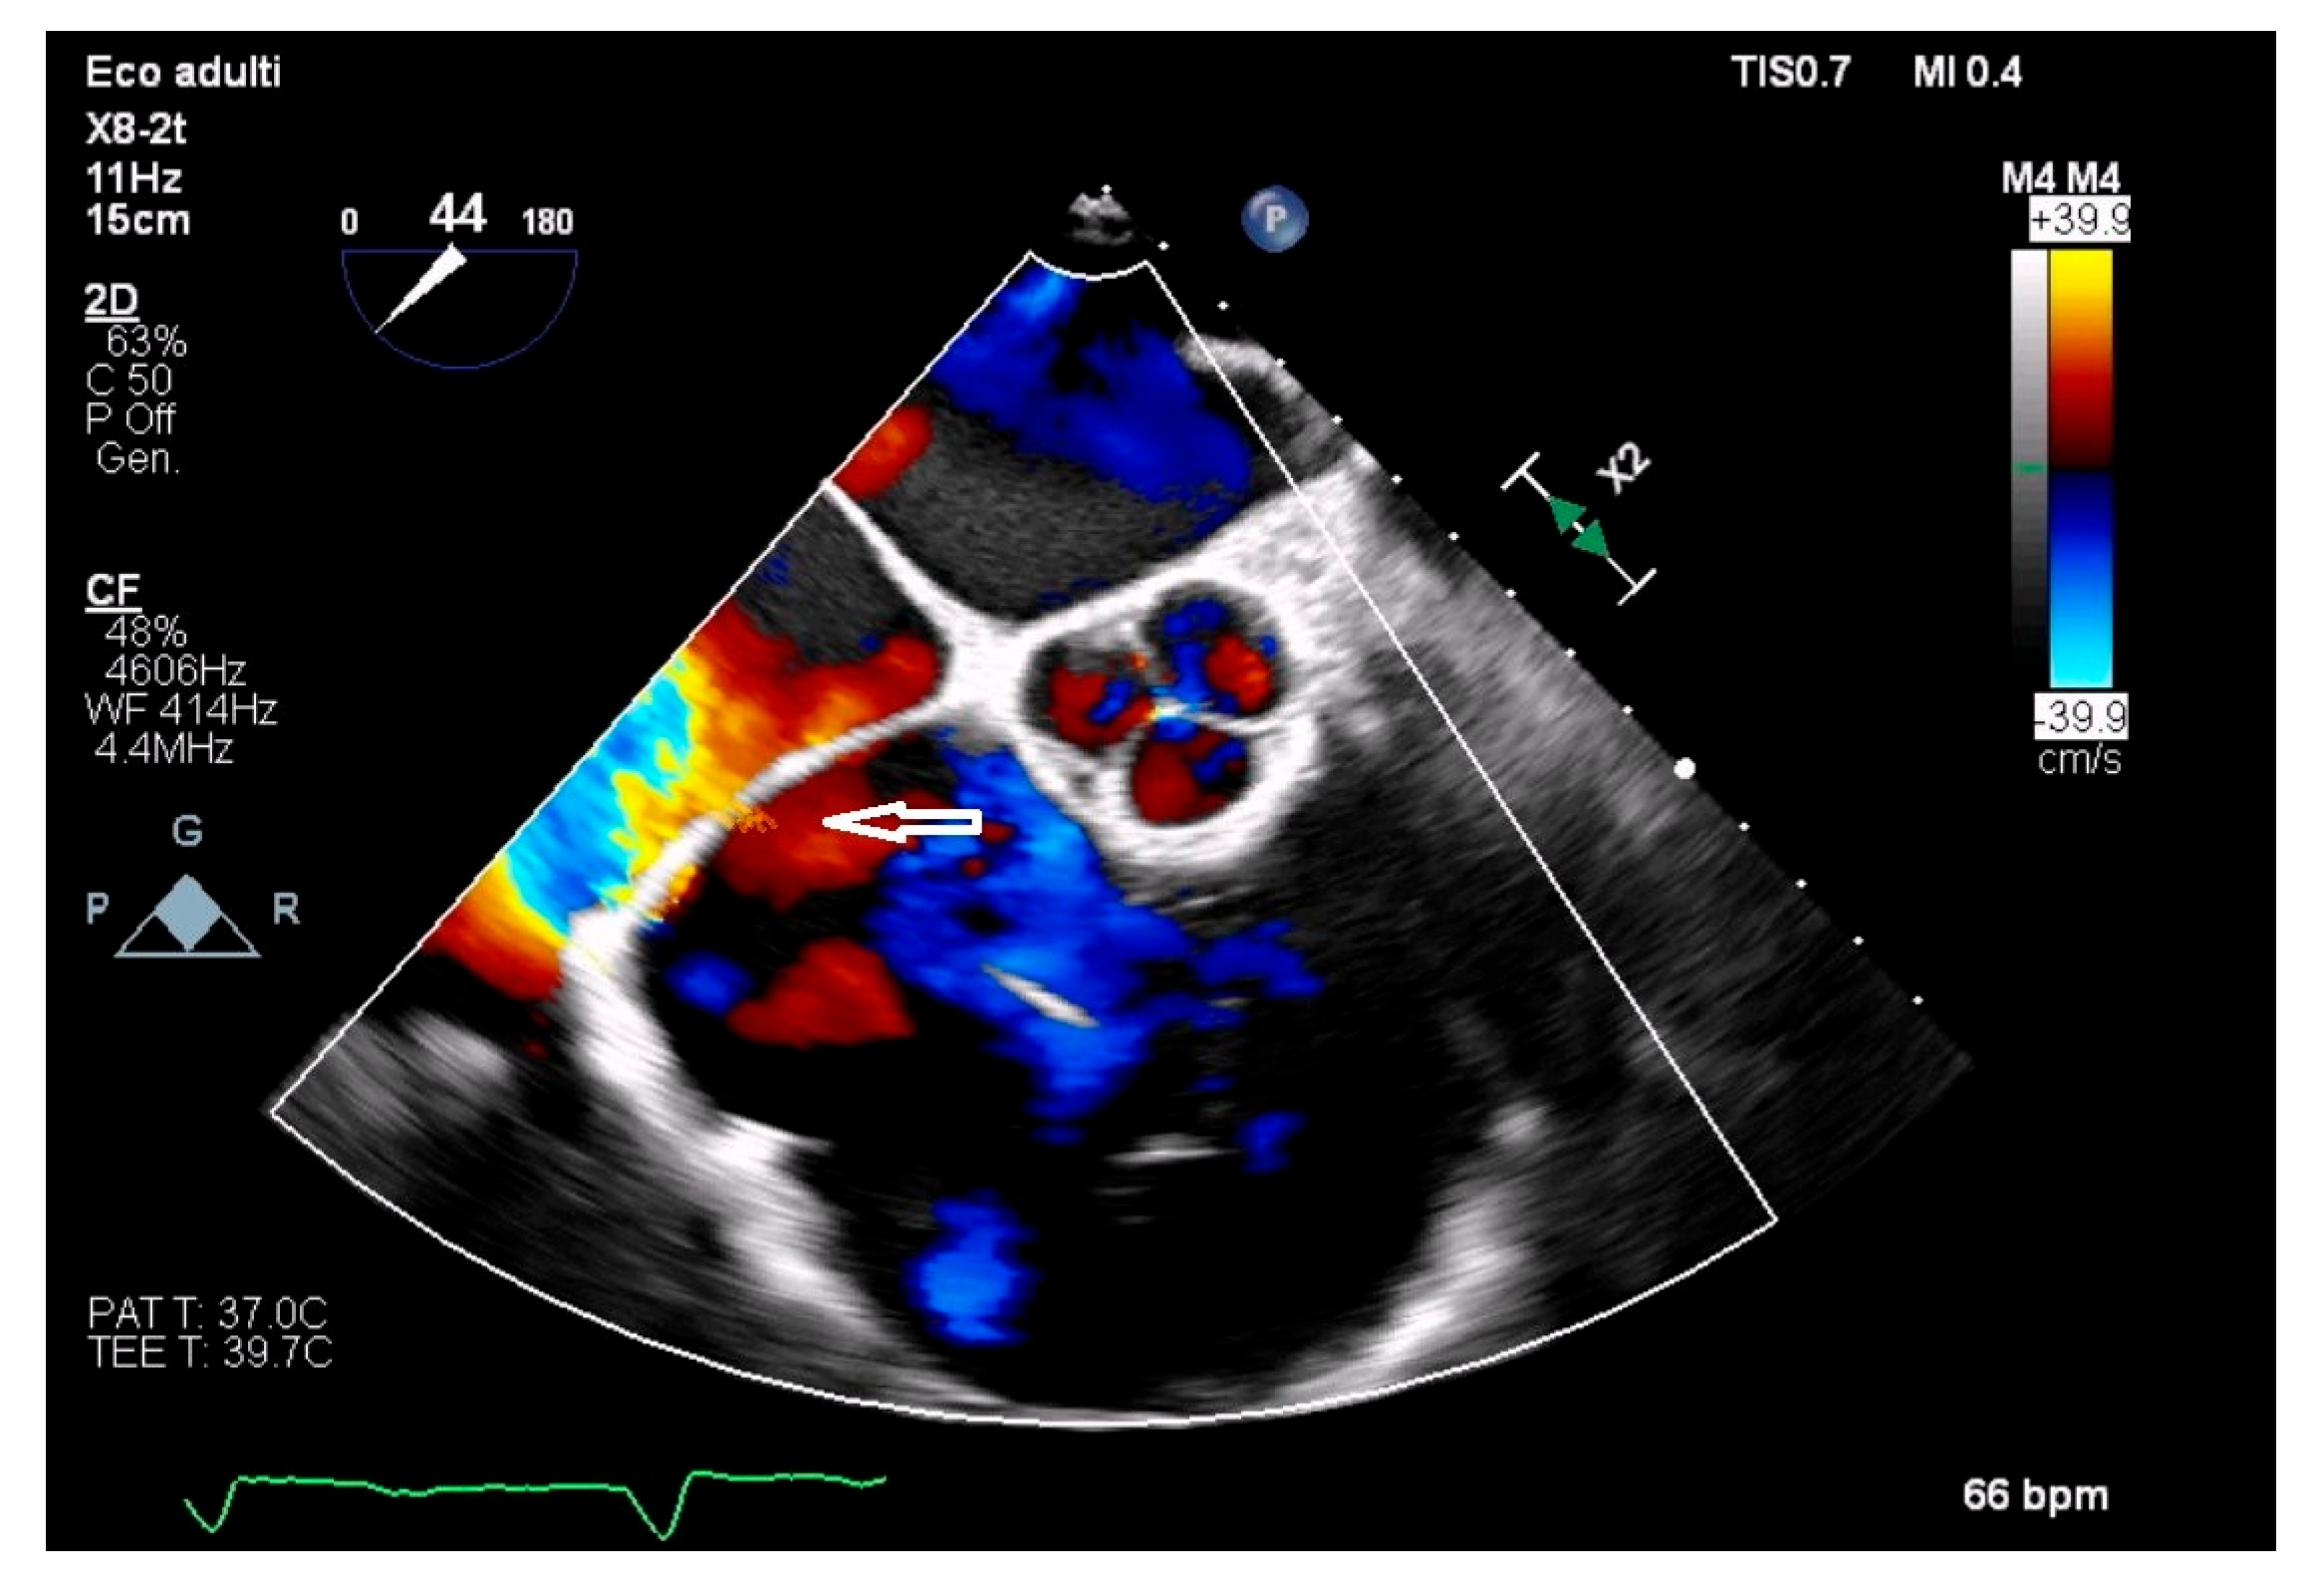

- Sozzi, F.B.; Montanaro, C.; Bacà, L.; Viani, G.M.; Zilocchi, M.; Canetta, C.; Meazza, R.; Pavone, L.; Lombardi, F. Cor Triatriatum Dexter Associated with Atrial Septal Defect: Management in a Complex Clinical Case. Echocardiography 2017, 34, 1725–1729. [Google Scholar] [CrossRef]